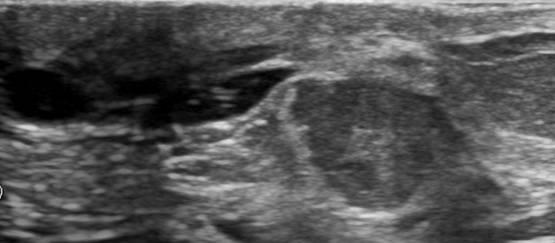

Ung thư vú

» Thông tin: Nữ giới – 69 tuổi.

» Lâm sàng: Kiểm tra sức khỏe.